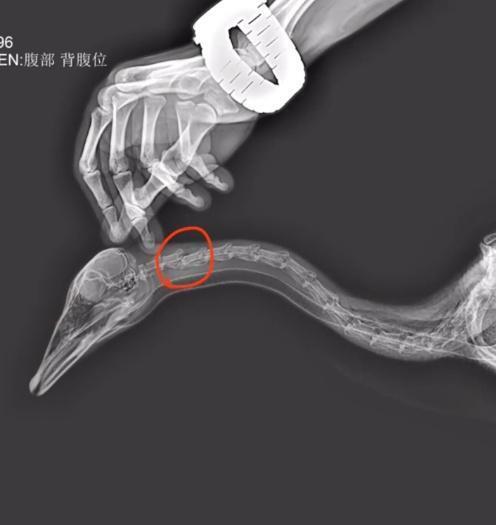

据悉,游客踢大雁,造成了大雁颈椎第二节骨折,最终死亡。